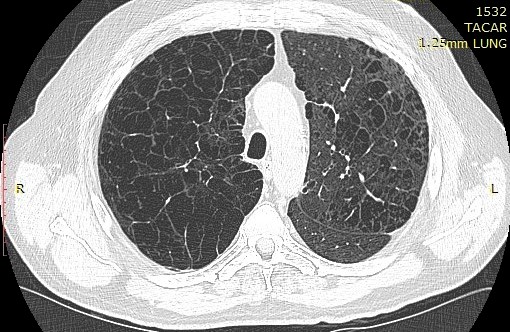

Síndrome de dificultad respiratoria aguda: causas, fisiopatología y fenotipos

06 septiembre 2022

Este es el primero de una serie de tres artículos sobre el síndrome de dificultad respiratoria aguda (el artículo 3 aparece en The Lancet Respiratory Medicine ). Lancet, 4 de septiembre de 2022